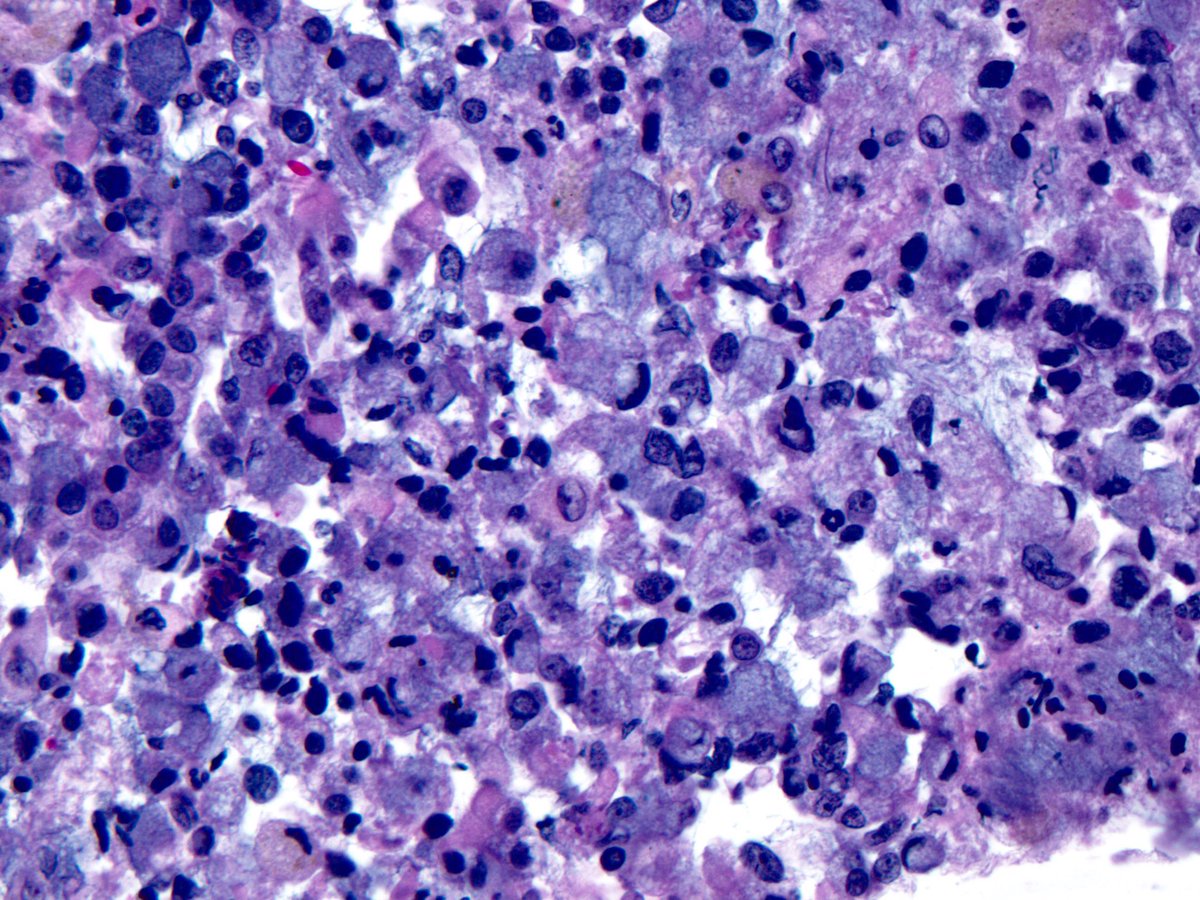

Primary effusion lymphoma (PEL), Large cells with round to irregular nuclei, prominent nucleoli, and abundant cytoplasm. HHV-8 stain on cell block: Granular/ speckled/ dotted nuclear staining. Loss of Pan-B cell markers.

#Hemepath#HemepathMDApic.twitter.com/QPHU8uaTrS